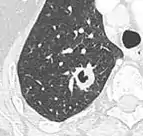

Lung nodule abutting a pulmonary cyst.[9]

• A lung nodule abutting a pulmonary cyst is a rare finding, yet indicating cancer.[9]